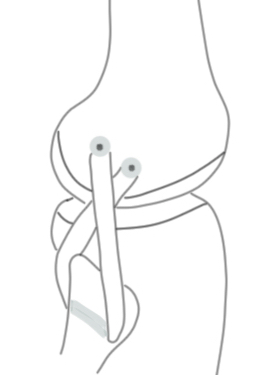

C. Arciero reconstruction (single graft reconstruction of LCL and Popliteus)

Concept

- drill LCL and popliteus tunnels as per LaPrade

- single tunnel in fibular

- reconstruction popliteus and LCL with single graft